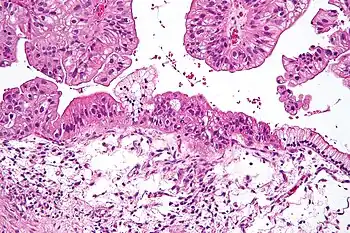

| Micrograph of a mucinous ovarian carcinoma stained by H&E | |

Mucinous

Mucinous tumors include mucinous adenocarcinoma and mucinous cystadenocarcinoma.[29]

Mucinous adenocarcinoma

Mucinous adenocarcinomas make up 5–10% of epithelial ovarian cancers. Histologically, they are similar to intestinal or cervical adenocarcinomas and are often actually metastases of appendiceal or colon cancers. Advanced mucinous adenocarcinomas have a poor prognosis, generally worse than serous tumors, and are often resistant to platinum chemotherapy, though they are rare.[29]